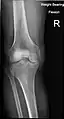

Knee X-ray

Knee X-ray (weight bearing)

Knee X-ray (weight bearing, flexion)